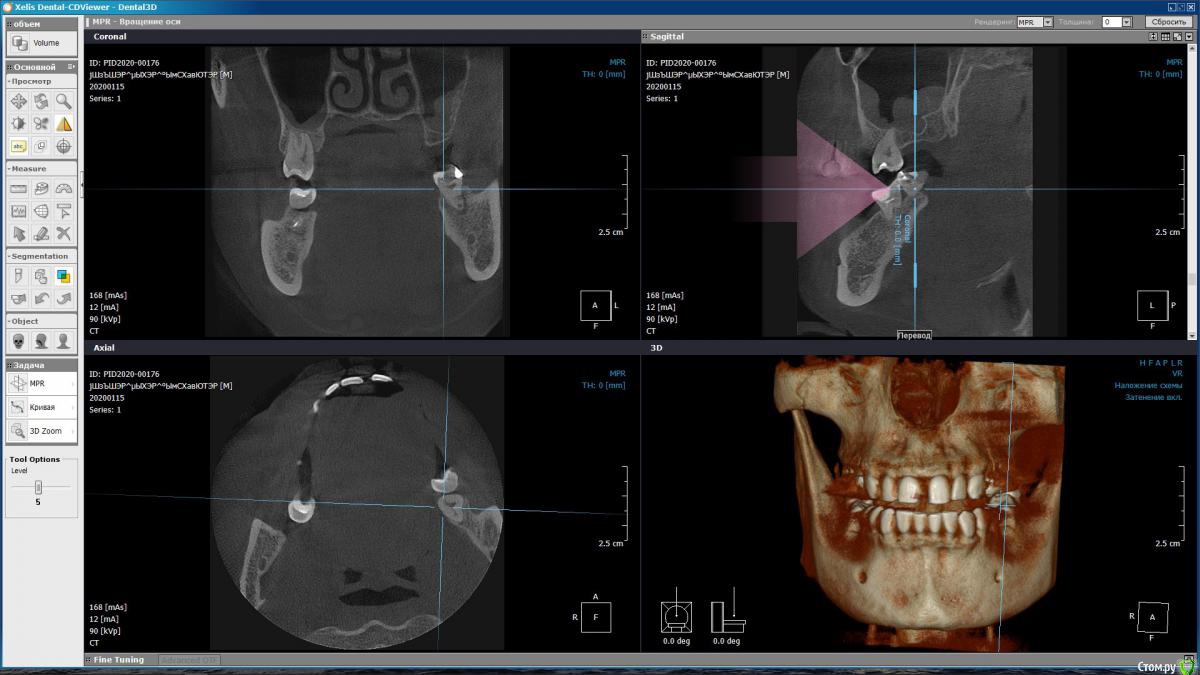

m-e-a Опубликовано 19 января, 2020 Автор Поделиться Опубликовано 19 января, 2020 (изменено) Сделала срезы как смогла, не умею я смотреть КТ Изменено 19 января, 2020 пользователем m-e-a Ссылка на комментарий

red_butler Опубликовано 19 января, 2020 Поделиться Опубликовано 19 января, 2020 На представленных срезах, показаний к удалению не увидел. Нужно смотреть очно и «крутить» Кт Ссылка на комментарий